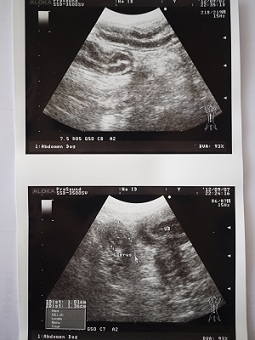

一番、心配していた子宮のエコー。

上は十二指腸あたりのエコーで、下が子宮。

膀胱が物凄く小さく写っていました。

蓄膿症の傾向は出ていないとのこと。

エコーでも、今の病態が伺えるものが見付からなかった。